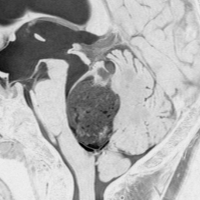

思春期の女の子にできた小脳腫瘍です。とても大きく見えますがほとんどが水たまり(のう胞といいます)。第4脳室が腫瘍で圧迫されて閉塞性水頭症になりました。のう胞の中に出血がありますが毛様細胞性星細胞腫では腫瘍内出血をしばしば見ます。右の写真で脳室が大きくなっています。こんなに大きいのに小脳症状は全くなくて,頭痛と嘔吐が症状でした。

赤で塗ったところだけが毛様細胞性星細胞腫です。これを取れば治ります。簡単な手術ですし後遺症も残りません。